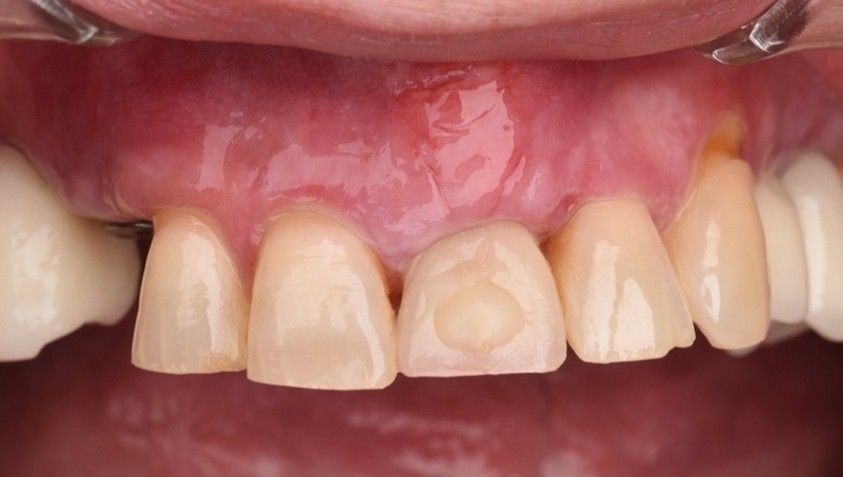

El implante se mantuvo en fase provisional durante un periodo aproximado de cuatro meses desde su colocación. Tras esta fase de provisionalización, se realizó la toma de impresión analógica mediante un coping de impresión personalizado, diseñado para reproducir de forma precisa el perfil de emergencia previamente modelado con la restauración provisional (Figuras 11 y 12). A partir de estos registros, se confeccionó e instaló la corona definitiva atornillada, con una oclusión suavizada para evitar sobrecargas del implante (2.1i). La imagen clínica (Figuras 13 y 14) y el CBCT postoperatorio (Figura 15) evidencian una situación clínica y radiológica favorable, con estabilidad de los tejidos periimplantarios a los cuatro años de seguimiento.

Resultados: El seguimiento clínico y radiológico evidenció una correcta osteointegración, estabilidad de los tejidos periimplantarios y un resultado estético satisfactorio, mantenido a los cuatro años.

Results: Clinical and radiographic follow-up demonstrated successful osseointegration, stable peri-implant tissues, and a favorable esthetic outcome maintained at four years.